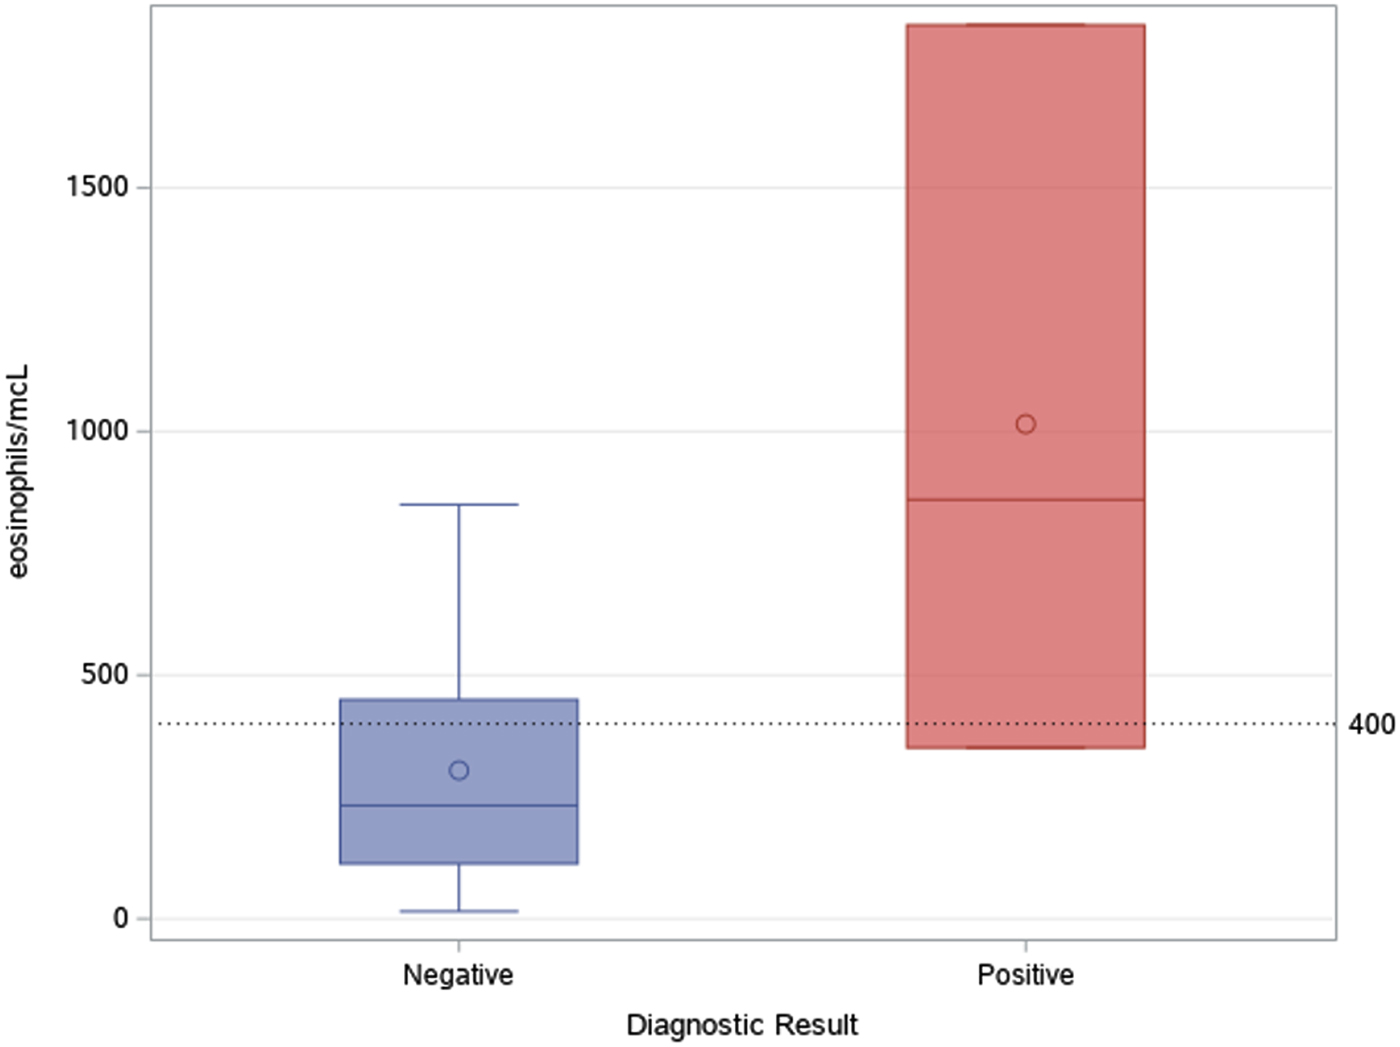

As shown in Figure 4, most tests were prescribed in the first semester of the activities (August 2017–February 2018): accounting for 74.4% of tests performed in the whole study period. Two patients out of 42 (4.8%) were found positive to serological screening (one autochthonous patient and one immigrant), but an additional autochthonous patient was diagnosed in the same study period by gastric biopsy. Two of the positive patients were born in San Marino, aged >80 years and had no history of travels outside San Marino/Italy (‘autochthonous cases’). The other positive patient was a 31-year-old man born in Nigeria and arrived in Europe (Italy first, then San Marino) in 2003. Median values of eosinophil count was 860 (IQR 351–1834) for positive patients, and 232 (IQR 113–449) for negative patients, as shown in Figure 5. Of note, the two autochthonous cases had moderate-high eosinophilia (from 860 to 1834 cells/μl upon diagnosis), while the patient from Nigeria had an eosinophil count of 351 cells/μl. All patients with positive serology presented compatible symptoms, in particular all patients reported abdominal pain and/or diarrhoea. The Nigerian patient had an obstruction of the bowel. One of them also reported weight loss and hyporexia. None of them was immunocompromised. The two patients from San Marino received treatment with ivermectin, with good clinical response. The African patient left San Marino before receiving treatment.

Fig. 5. Median and IQR values of eosinophil count in patients with positive and negative serological result.